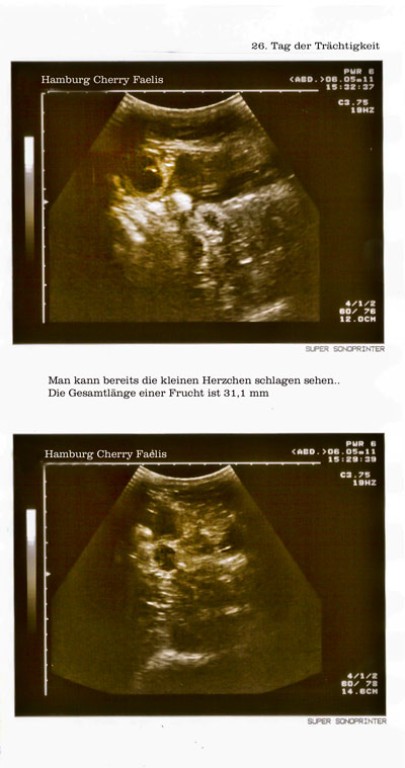

Die ersten Ultraschallbilder....

Ein Wunder der Natur und ein Wunder der Technik.

Es ist aufregend und schön die Möglichkeit zu haben dieses Meisterwerk der Natur

ein kleines Bisschen in der Entwicklung zu beobachten.....